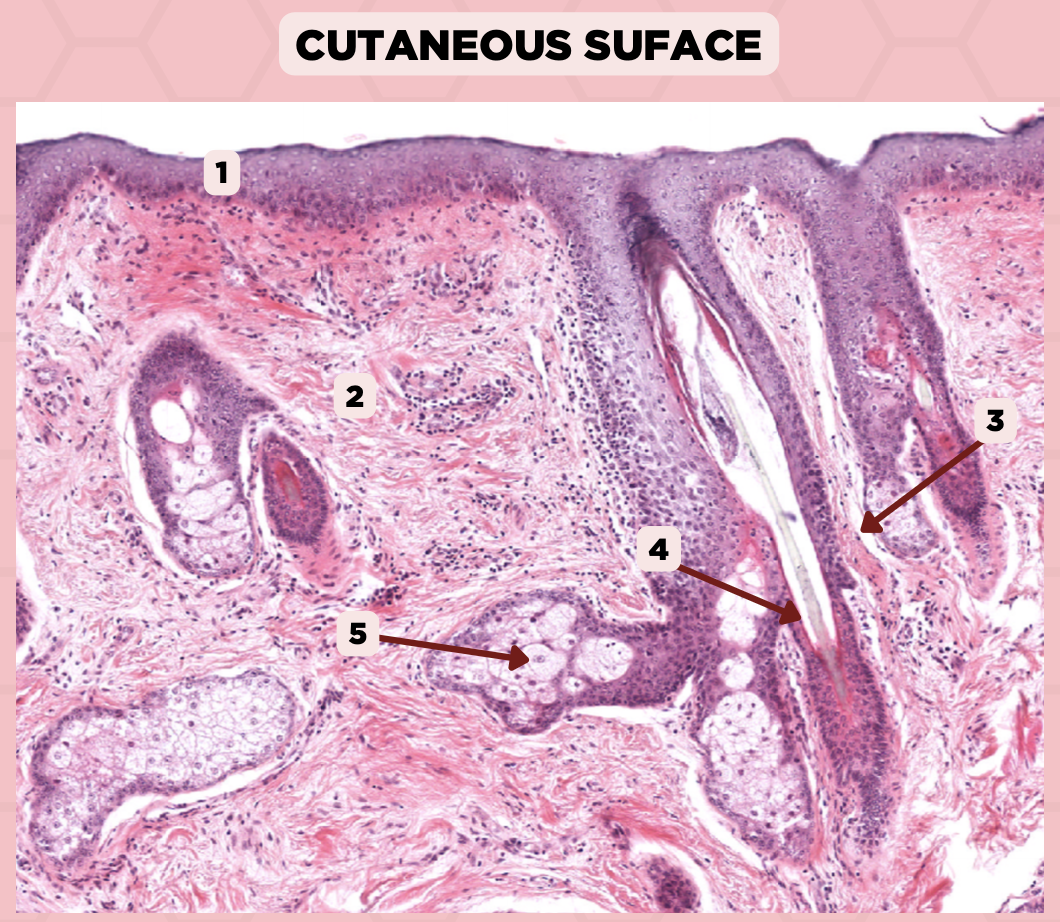

Lip

What specimen is being showed in the picture?

Epidermis

Identify the structure labeled as 1.

Dermis

Identify the structure labeled as 2.

Arrector Pilli Muscle

Identify the structure labeled as 3.

Hair Follicle

Identify the structure labeled as 4.

Sebaceous Glands

Identify the structure labeled as 5.

Lip

What is the specimen showed in the picture?

Epidermis

Identify the structure labeled as 1.

Dermis

Identify the structure labeled as 2.

Arrector Pilli Muscle

Identify the structure labeled as 3.

Hair Follicle

Identify the structure labeled as 4.

Sebaceous Glands

Identify the structure labeled as 5.